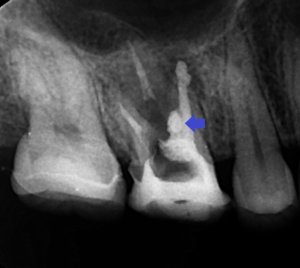

上の画像は、根管充填とパーフォレーションリペア時の

レントゲン画像です。

根管充填とパーフォレーションリペアは、

MTAセメントを使用しています。

青い矢印の先がパーフォレーションリペア部です。